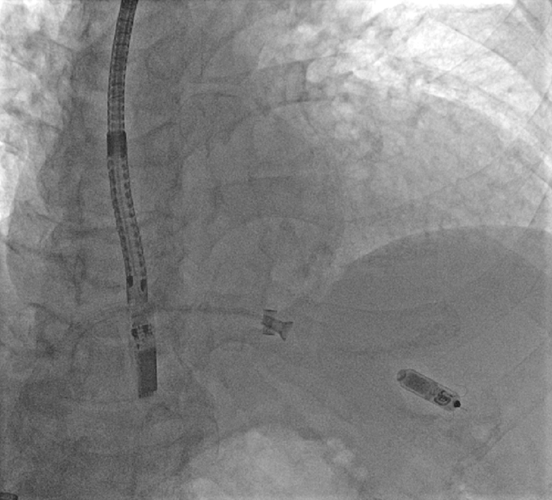

Specjaliści elektrofizjolodzy: dr hab. Maciej Kempa i dr Szymon Budrejko przeprowadzili 3 zabiegi implantacji stymulatorów bezelektrodowych (Medtronic Micra) z wykorzystaniem stałego monitorowania echokardiograficznego przezprzełykowego. Wartym podkreślenia novum jest użycie nowoczesnej sondy mini 4D TEE. Monitorowanie prowadziła kierownik Kliniki prof. Ludmiła Daniłowicz-Szymanowicz.

– Użyta do monitorowania głowica przezprzełykowa mini 4D jest dwukrotnie cieńsza niż głowica tradycyjna, przez co jest zdecydowanie lepiej tolerowana przez pacjenta. Ma to szczególne znaczenie, ponieważ zabiegi takie przeprowadzane są bez stosowania znieczulenia ogólnego ani sedacji – pacjent jest więc w pełni świadomy. Dotychczas tego typu procedury przeprowadzane były tylko pod kontrolą fluoroskopii (rodzaj prześwietlenia z wykorzystaniem promieni rentgenowskich) – wyjaśnia prof. Ludmiła Daniłowicz-Szymanowicz.

Możliwość unikatowego monitorowania echokardiograficznego służy lepszej wizualizacji w trakcie zabiegu, podczas którego stymulator bezelektrodowy powinien być umiejscowiony dokładnie w obrębie przegrody międzykomorowej, a nie ściany wolnej prawej komory, co prowadzić mogłoby do poważnych powikłań. Zastosowanie tak precyzyjnej wizualizacji echokardiograficznej zwiększa bezpieczeństwo chorego, jak również przyczynia się do skrócenia czasu zabiegu.